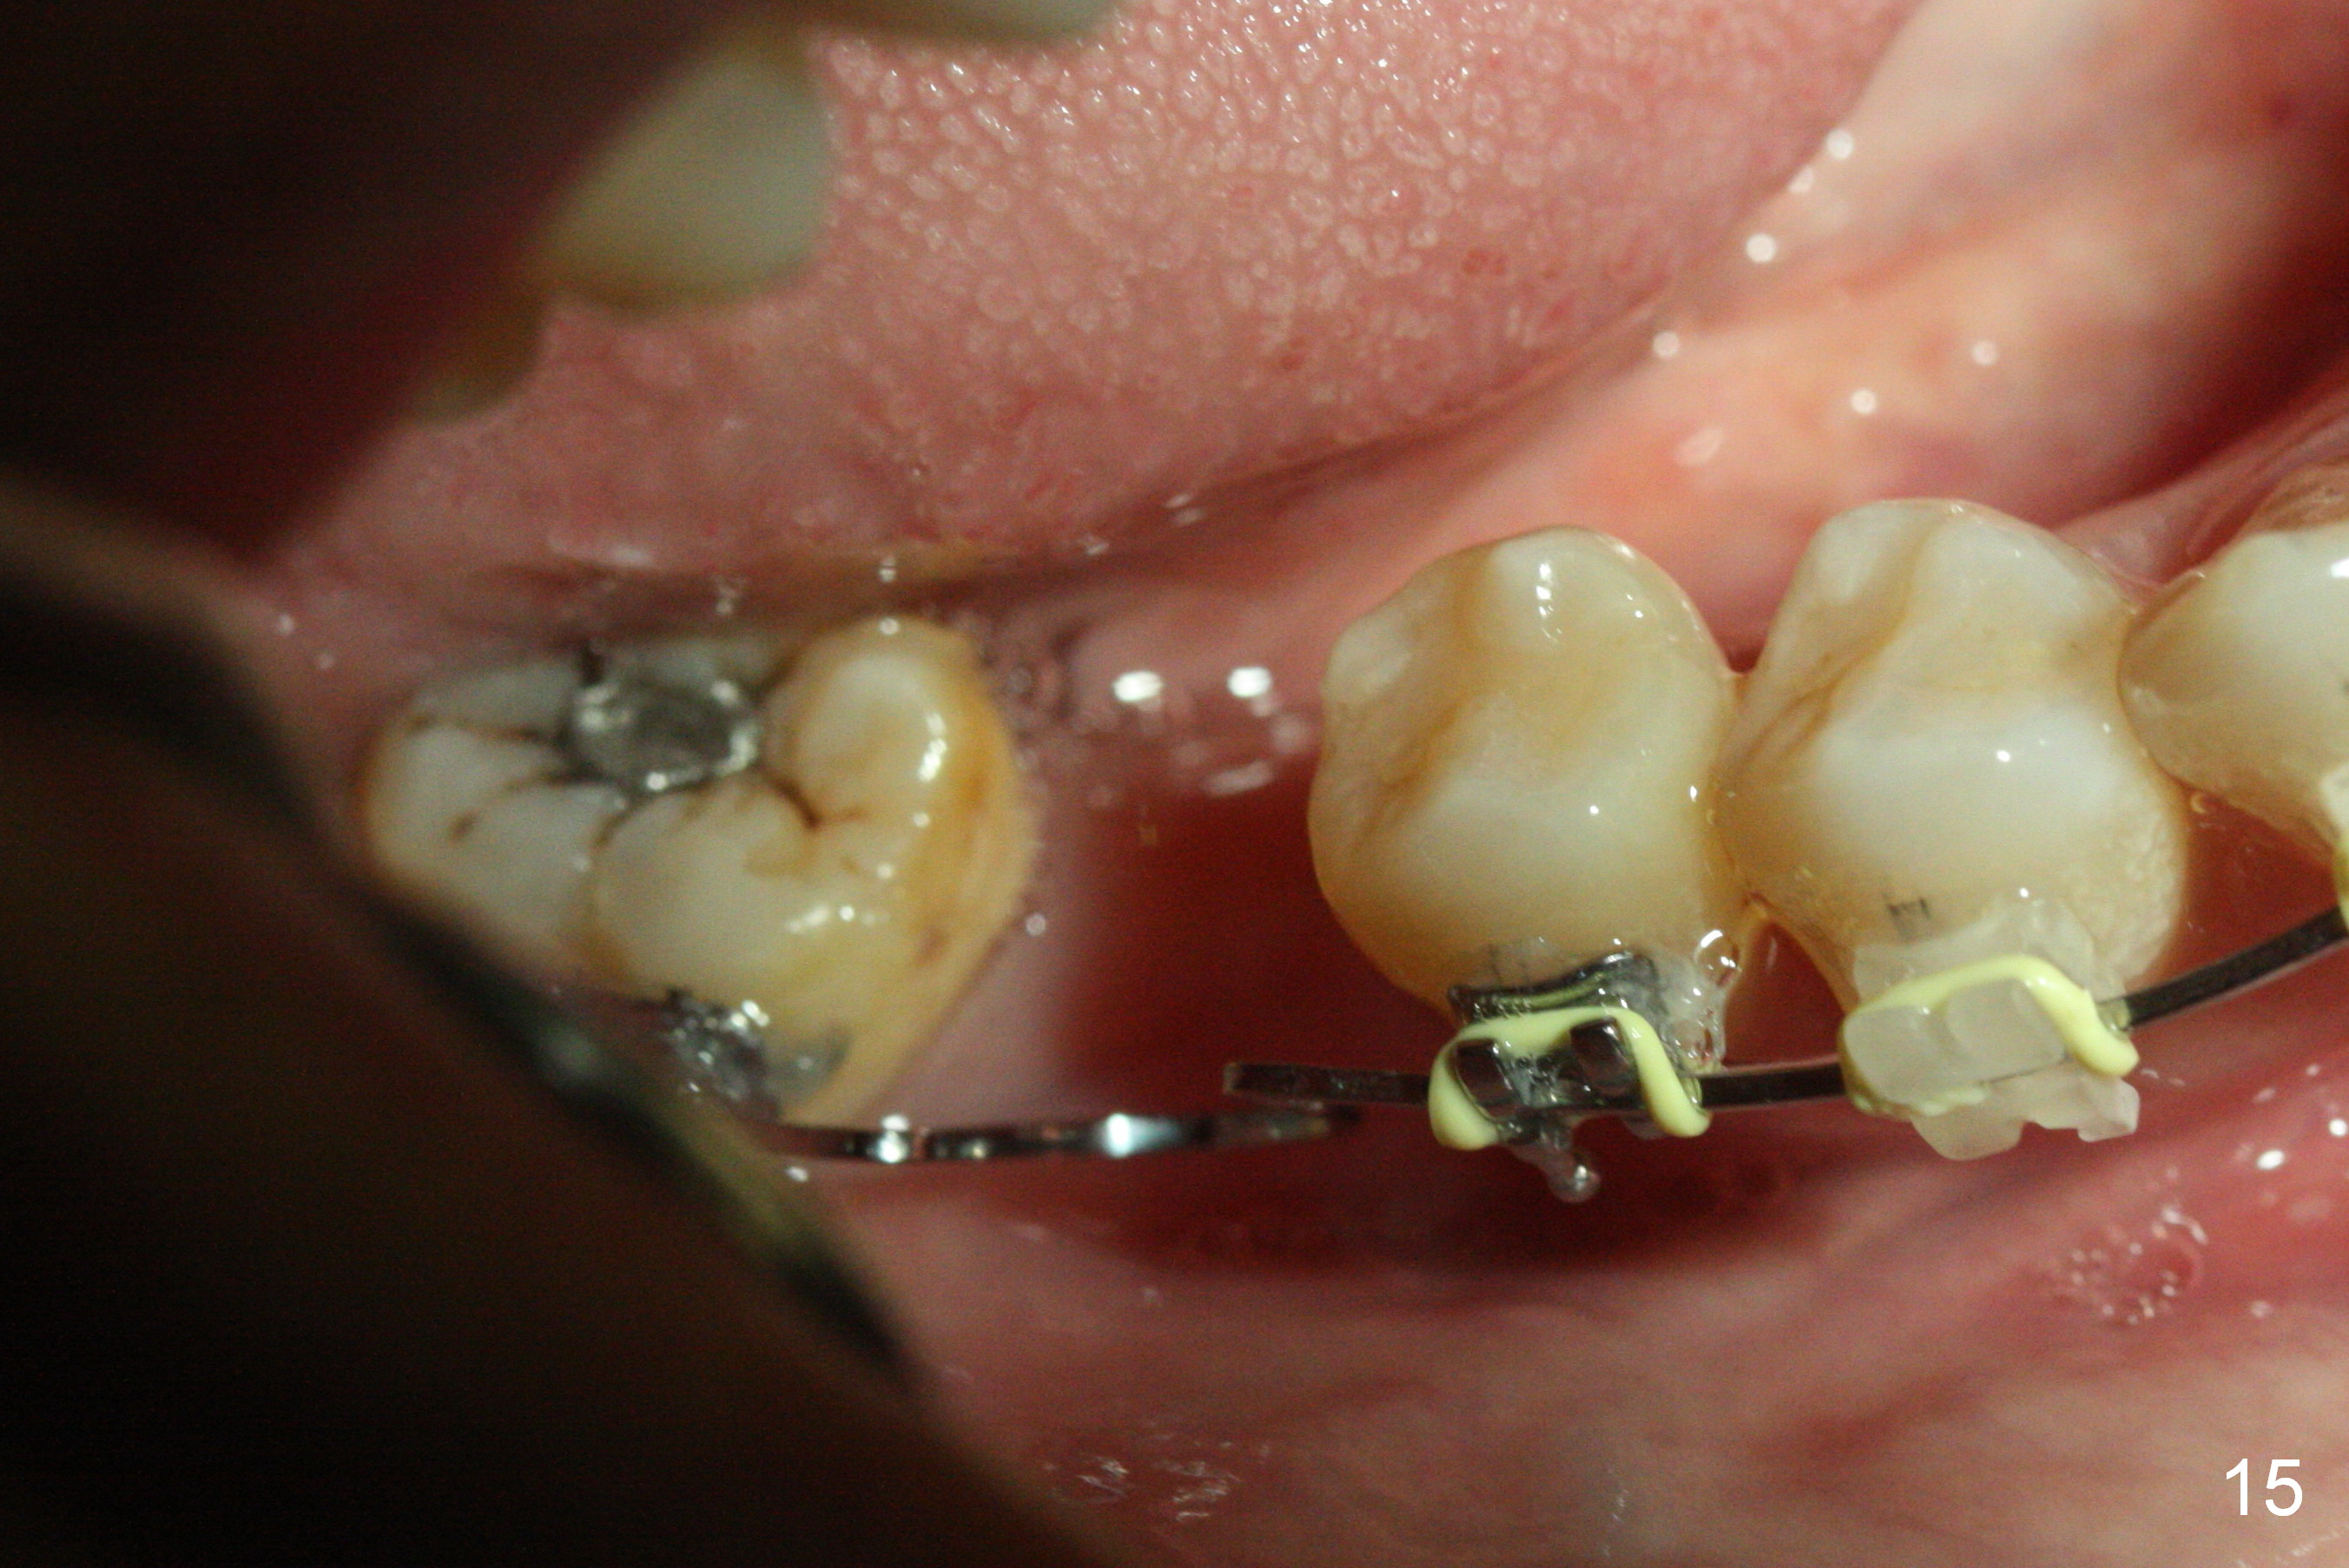

Show the patient that the tooth #31 is severely mesially tilted with reduction in the mesiodistal width for implant placement (Fig.5,7). The tooth #32 is severely malpositioned (linguoversion, Fig.6). It is extremely difficult to gain space for the implant without #32 extraction.

Nearly 6 months post banding, the teeth #20-22 have been distalized (Fig.14). An omega loop has been introduced between #29 and 31 for a month. When the loop is activated, there is pressure upon the tooth #29. It appears that interarch retraction between #2 DL and #31 ML is the most effective (Fig.16).